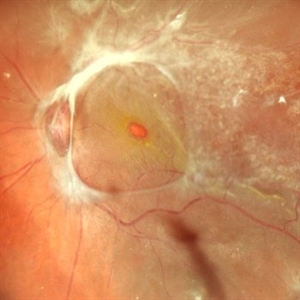

Combined Retinal Detachment With Macular Hole

Combined Retinal Detachment With Macular Hole

Sep 28 2024 by Tejaswita Verma

Fundus image of the LE of a 67 year old diabetic, hypertensive female with CF 3metres vision showing combined RD with FTMH, in a pseudophakic eye. She was lost to follow up status post 2 anti VEGF injections received 8 months back due to typhoid fever.

Photographer: DR. TEJASWITA VERMA

Imaging device: MIRANTE

Condition/keywords: full thickness macular hole, proliferative diabetic retinopathy (PDR), tractional retinal detachment